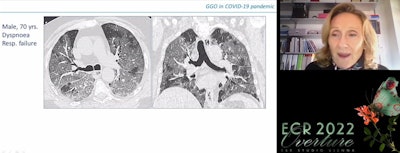

Dr. Marie-Pierre Revel, PhD, of Paris Descartes University's Cochin Hospital in Paris, France, presenting on March 2 at ECR 2022 Overture."These are what I would call 'false false-negatives,' " Revel noted during a special session at the recent ECR 2022 Overture meeting.

Differential diagnosis on CT in COVID-19 patients is difficult, primarily because CT findings have low specificity due to their overlap with a number of other conditions, according to Dr. Anna Rita Larici of the Catholic University of Sacro Cuore in Rome, Italy.

"Since the beginning of our experience, we've learned COVID-19 pneumonia should be considered a great radiological mimicker," she said.

Other conditions to consider include diffuse alveolar damage, acute respiratory distress syndrome (ARDS), alveolar proteinosis, and pneumocystis jiroveci pneumonia. However, CT-related findings are significantly more common in COVID-19 compared with other viral respiratory illnesses, Larici said.

Dr. Anna Rita Larici of the Catholic University of Sacro Cuore in Rome, Italy, presenting on March 2 at ECR 2022 Overture.Primary CT features in favor of COVID-19 pneumonia include ground-glass opacification (GGO) -- patchy, peripheral, bilateral, and basal predominant distributions -- and enlarged pulmonary vessels, while features against COVID-19 pneumonia include the following:

- Lack of GGO

- Lobar or nonsegmental consolidation

- Cavitation/abscesses

- Tree-in-bud opacities

- Lymphadenopathy

- Pleural effusion

- Pericardial effusion

"The combination of CT features with clinical data, history, and lab and microbiology in the multidisciplinary team context can substantially improve the accuracy of diagnosis and patient management," Larici said.